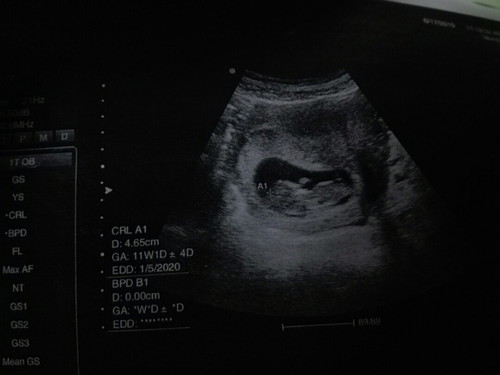

แม่ๆคนไหนตรวจพบเป็นธาลัสซีเมียบ้าง

อยากทราบว่าถ้าเป็นพาหะกับโรคอันไหนยังอุ่นใจกว่ากันกังวลมากๆเจาะทั้งพ่อปม่รอฟังผลอีกที

ของเราเป็นพาหะค่ะ แต่โชคดีที่สามีปกติเลยไม่อันตรายค่ะ แต่ถ้าเป็นพาหะทั้งคู่อันนี้ก็มีความเสี่ยง รึถ่าเราเป็นโรคแล้วสามีปกติ ก็ไม่เป็นไรค่ะ